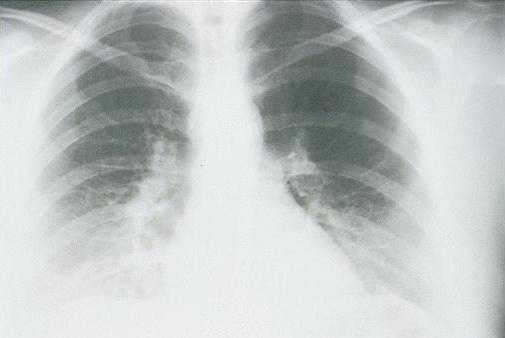

Radiologic Findings

HPS has a characteristic radiological evolution, beginning with minimal changes of interstitial pulmonary edema, progressing to alveolar edema with severe bilateral involvement. Pleural effusions are common and are often large enough to be evident radiographically. Heart size is usually normal. Cardiac silhouette size on chest radiographs is usually normal.

Approximately one-third of patients show evidence of pulmonary edema in the initial radiograph. Forty-eight hours after the initial radiograph, virtually all patients demonstrate interstitial edema and two-thirds have developed extensive bibasilar or perihilar airspace disease.

This radiograph shows the interstitial changes of early HPS. At the lung bases are Kerley B lines, short linear opacities which are perpendicular to the pleural surfaces. The longer linear opacities radiating from the lung hilum are known as Kerley A lines. Together these findings are classically seen in heart failure, but are also seen in HPS. Peribronchial cuffing is also seen well on this film. The bronchi viewed end on are surrounded by a “cuff” of edema. This makes the bronchi appear as prominent circular opacities, appearing as “ring-like” shapes next to pulmonary blood vessels.

The lack of peripheral distribution of the initial airspace disease, the prominence of interstitial edema and the presence of pleural effusions early in the disease process help distinguish HPS from ARDS. There is, however, overlap in the radiographic appearance of the two diseases. Atypical pneumonias such as that caused by mycoplasm pneumonia can produce radiographic findings similar to early HPS, although the clinical illness tends to be much less severe.

Hyperacute hypersensitivity reactions, mitral stenosis, acute myocardial infarctions, all can cause interstitial edema with a normal heart size, and are also in the radiologic differential diagnosis of early HPS.